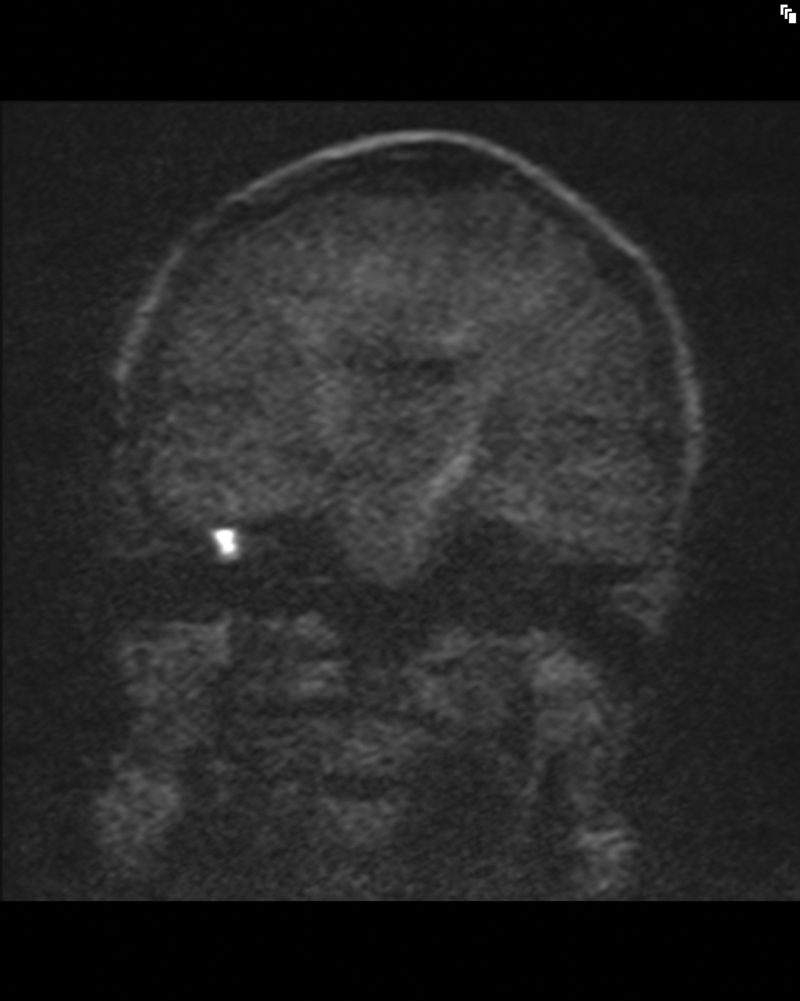

The apparent diffusion coefficent (ADC) map is also reconstructed after the scan using the diffusion scan raw data and this allows the ADC value of the lesion to be calculated [4]. Cholesteatoma, by virtue of its keratin content, produces high signal intensity on DWI obtained with b-values of 800 or 1000 s/mm2 (Figure 1) and corresponding low signal on the ADC map. The high signal of cholesteatoma on diffusion weighted images is a result of restricted molecular diffusion but also due to a ‘T2 shine through effect’ that occurs in tissues with high T2 signal intensity and ADC values less than brain [1, 2]. The ADC values of postoperative middle ear cleft cholesteatoma have been shown to be significantly lower than that of non-cholesteatomatous tissue [4].

Figure 1: Coronal HASTE diffusion weighted b1000 image shows high

signal cholesteatoma at post-operative right middle ear cleft.